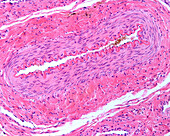

13613519 - Layers of a large vein wall, light micrograph

13613518 - Layers of a large vein wall, light micrograph

13613504 - Muscular artery, light micrograph